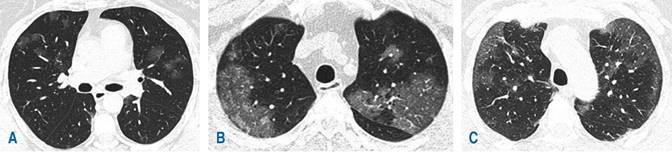

De acuerdo con los hallazgos tomográficos, el patrón predominante en 39% (22) de los casos fue patrón mixto (Figura 1) caracterizado por patrón en vidrio deslustrado, combinado con zonas de consolidación, seguido de patrón empedrado (Figura 2) y patrón en vidrio deslustrado único (Figura 3) con 30% (17) y 29% (16), respectivamente. La localización de las lesiones fue bilateral en 88% (52) de los casos estudiados con mayor involucro de lóbulos inferiores en 55% (31), seguido de afectación en lóbulos superiores en 36% (20). La distribución de las lesiones fue predominantemente subpleural en 48% (27) de los casos estudiados (Figura 4), seguida de afectación con distribución en parches en 20% (11) (Figura 5). En otros hallazgos predominaron las linfadenopatías con 25% (14), seguidas de las atelectasias en 23% (13) (Tabla 2).

Figura 2: Tomografía computarizada de tórax en ventana pulmonar, A) patrón en empedrado, el cual consiste en vidrio deslustrado asociado con engrosamiento de los septos inter y/o intralobulillares (flechas huecas), lo cual le confiere un aspecto en «empedrado» también conocido como Crazy Paving (imagen D); B) empedrado de distribución central; C) patrón en empedrado de distribución clásicamente subpleural.

Figura 3: Tomografía computarizada de tórax en ventana pulmonar, patrón en vidrio deslustrado. A) Distribución parcheada de las lesiones en lóbulos superiores. B y C) Incremento de la atenuación en vidrio deslustrado de distribución subpleural.